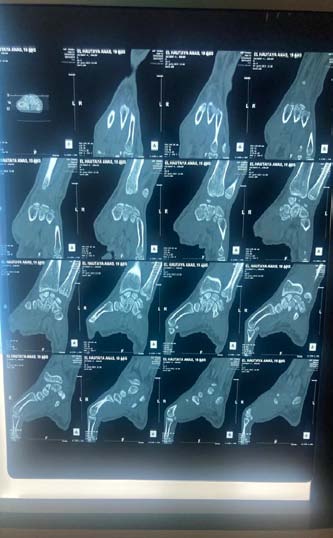

The standard radiographic assessment revealed a scaphoid fracture with an underlying gap, suggesting the possibility of a cyst or pseudarthrosis of the scaphoid (figure 1). The wrist CT scan confirmed the scaphoid fracture with a probable intraosseous cyst (figure 2). The patient underwent surgery via an anterior approach. Careful curettage of the cavity was performed after distraction of the fracture site. The bone defect was filled with autologous cancellous graft harvested from the lower metaphysis of the ipsilateral radius. Fracture stabilization was achieved with 2 pins (figure 3). The histopathological examination of the curettage specimen showed that the cyst wall was lined with flattened fibroblastic cells resembling synovial cells, without true epithelial appearance. There was no mucoid degeneration or myxoid transformation. The patient was immobilized for 2 months in a resin splint. After this period, the hardware was removed under local anesthesia. Several sessions of functional rehabilitation were initiated after plaster removal. At the latest follow-up at 6 months after treatment, the patient had regained good wrist function, with painlessness and resumption of leisure and professional activities.

From a radiological perspective, typical images show osteolytic lesions of a few millimeters in diameter, either solitary or multilobulated, accompanied by a peripheral rim of osteosclerosis [7]. This description corresponds to the lesion observed on our patient's radiographs, along with a discontinuity at the scaphoid neck, indicating a pathological fracture due to weakening of the scaphoid neck. Computed tomography, whether performed with or without contrast agent injection, allows for precise determination of the nature of the intracystic contents and any cortical involvement [1,7]. It also helps establish a surgical protocol by specifying the most appropriate approach, including the preferred surgical access route.